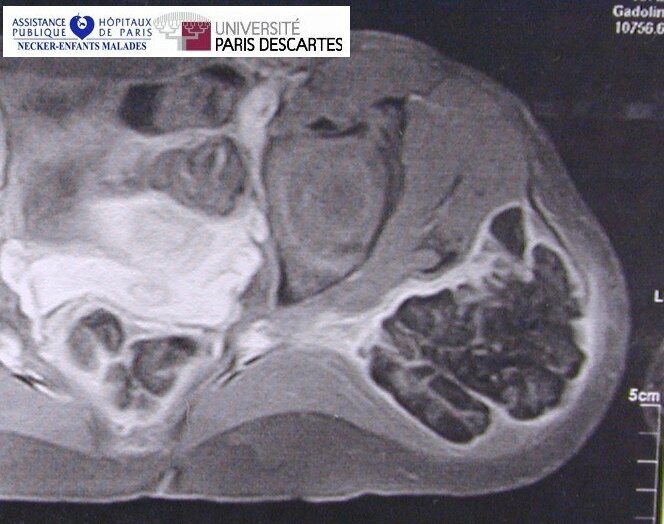

Tumoral Calcinosis